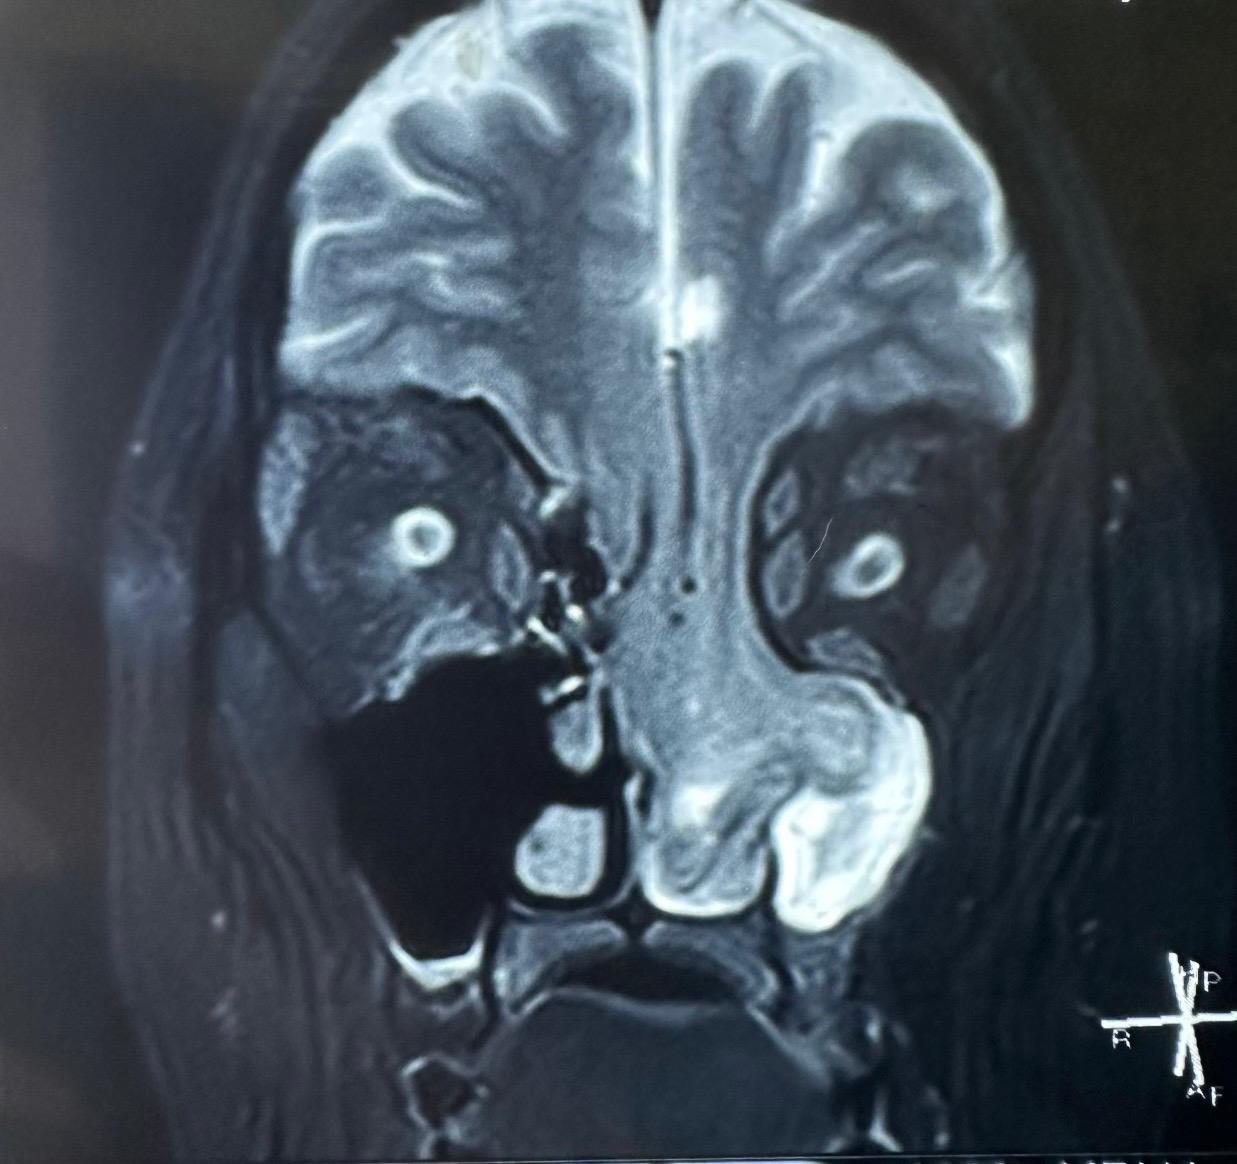

महिला कई महीनों से नाक बंद रहने और लगातार नाक बहने की शिकायत से परेशान थीं। जांच के बाद पता चला कि क्रेनियल बेस — यानी दिमाग और नाक की गुहा को अलग करने वाली पतली हड्डी — धीरे-धीरे घिस चुकी थी। इसके चलते दिमाग के ऊतक (Brain Tissue) नाक और मुँह के अंदर तक पहुँच गए थे, जो साफ़ दिखाई दे रहे थे।

“जब मरीज हमारे पास आईं, तो उन्हें केवल नाक बंद रहने और बहने की शिकायत थी। एंडोस्कोपिक जांच के बाद हमने दुर्लभ स्थिति का अंदेशा जताया। आगे की सीटी और एमआरआई स्कैन में पाया गया कि दिमाग का हिस्सा नैसल कैविटी में पहुंच चुका है। यह सर्जरी तकनीकी रूप से अत्यंत जटिल थी और इसमें उच्च स्तर की सटीकता की जरूरत थी। इस सफलता ने मल्टीडिसिप्लिनरी टीमवर्क और सटीक निदान के महत्व को दर्शाया।”

“यह मामला बेहद चुनौतीपूर्ण था क्योंकि दिमाग के साथ उसकी रक्तवाहिनियां भी नीचे सरक गई थीं। ज़रा-सी गलती जानलेवा स्ट्रोक का कारण बन सकती थी। दिमाग के आधे हिस्से को वापस उसकी जगह लाने और क्रेनियल बेस को दोबारा बनाने में बेहद सावधानी रखी गई। आज मरीज पूरी तरह स्वस्थ हैं और सामान्य जीवन जी रही हैं।”